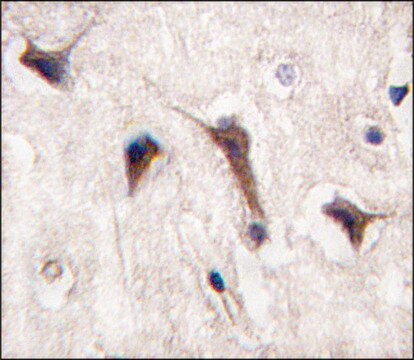

indirect ELISA: 1:1000, western blot: 1:100-1:500